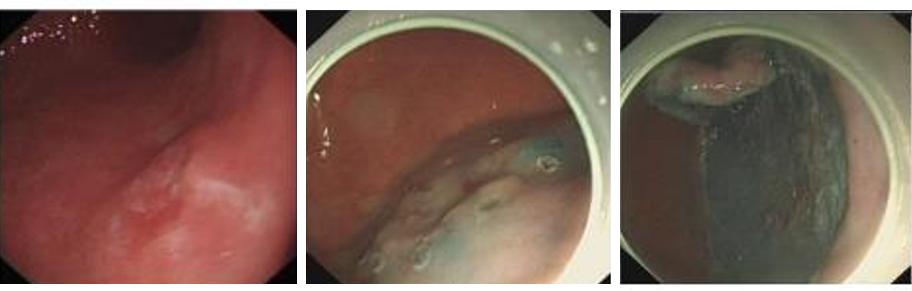

内镜检查若明确病灶属于消化道早癌,则可进行内镜下肿瘤切除,避免外科手术。由于消化道早癌病灶主要局限在黏膜层,在内镜下可以通过注射可吸收的或者吸收比较缓慢的液体,在黏膜层和肌层中间做个垫子,同时将癌组织和周围正常组织分离,然后用特殊的器械划开垫子层,把癌组织逐步剥离下来,即我们通常说的内镜下粘膜剥离术(ESD术)(图2-3)。

图2食管早癌治疗

内镜下完整切除早期食管癌

图3早期胃癌治疗内镜下完整切除早期胃癌